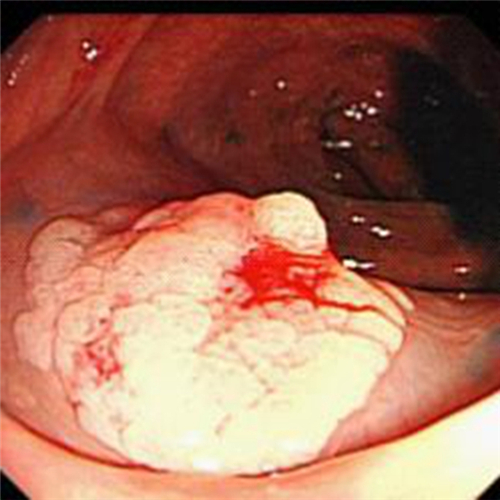

直腸息肉圖片

直腸息肉表現

直腸息肉早期

直腸息肉無蒂

直腸息肉切除

直腸息肉手術過程

直腸息肉糜爛的